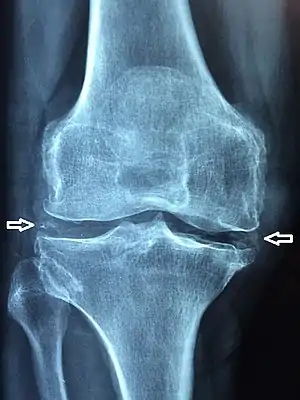

Chondrocalcinosis or cartilage calcification is calcification (accumulation of calcium salts) in hyaline cartilage and/or fibrocartilage.[1] It can be seen on radiography.

| X-ray of a knee with chondrocalcinosis | |

Chondrocalcinosis can be visualized on projectional radiography, CT scan, MRI, US, and nuclear medicine.[1] CT scans and MRIs show calcific masses (usually within the ligamentum flavum or joint capsule), however radiography is more successful.[1] At ultrasound, chondrocalcinosis may be depicted as echogenic foci with no acoustic shadow within the hyaline cartilage.[7] As with most conditions, chondrocalcinosis can present with similarity to other diseases such as ankylosing spondylitis and gout.[1]